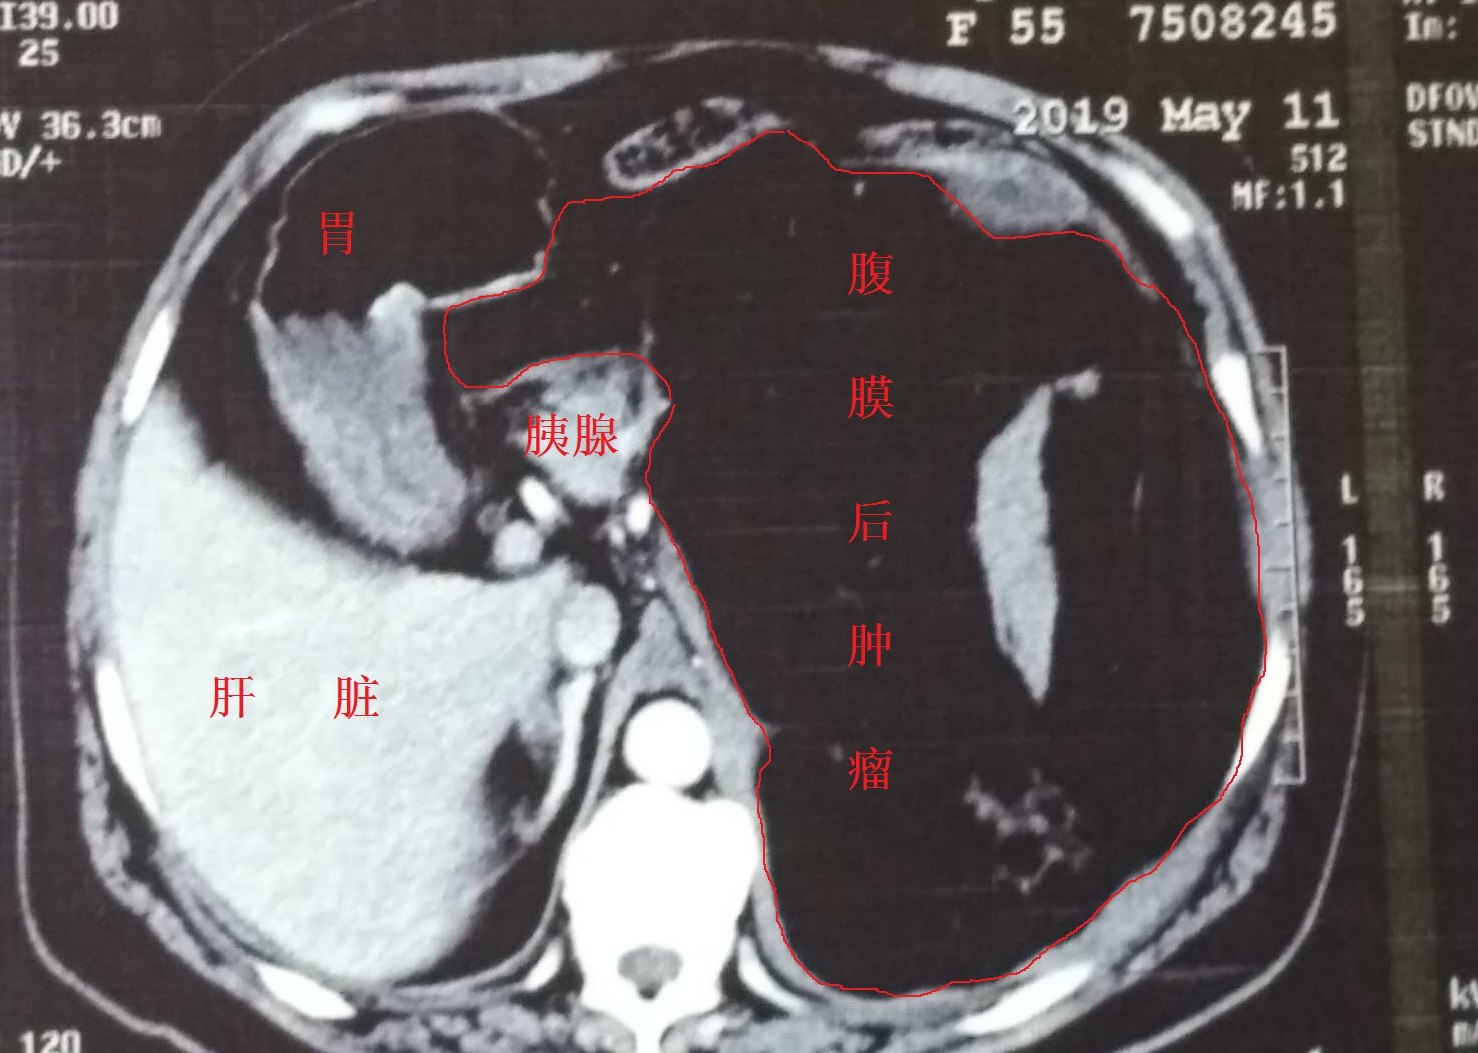

一例巨大腹膜后肿瘤合并自发性破裂大出血的患者获得成功救治 (原创)

图片尺寸1478x1053